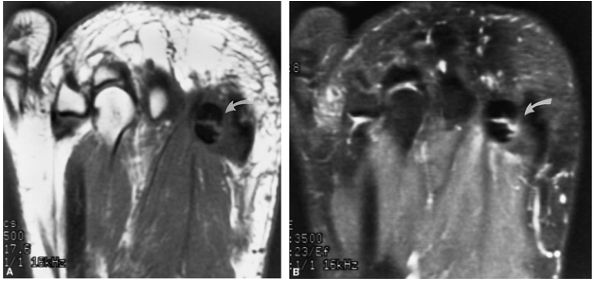

![]() |